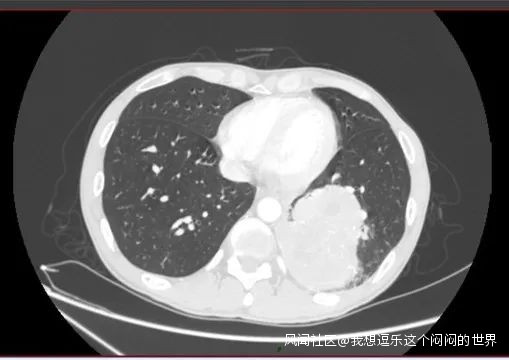

患者在家裏無法就診,同時出現了痰中帶血。直到6月再次就診,複查胸部CT,腫塊明顯增大,並出現了阻塞性肺炎。

左下肺佔位明顯增大,直徑約8cm

同時行PET-CT檢查,發現同側縱隔淋巴結出現了轉移(N2),所幸沒有遠處轉移(M0)。臨牀分期為cT4N2M0,IIIB期,暫時不考慮手術。